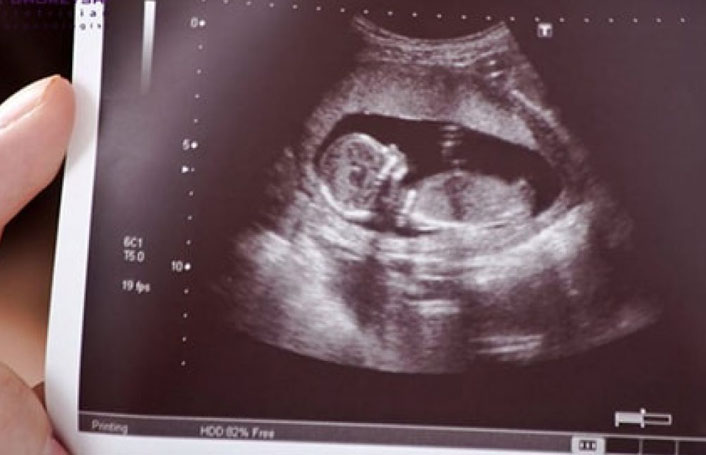

هماکنون زنان باردار در دوران بارداری خود و در هفته ۱۱ الی ۱۴ بارداری آزمایش غربالگری انجام میدهند تا مشکلات کوروموزمی و تمامی نواقصی که دارند در آن مشخص میشود و اگر غیرقابل درمان باشد، با تشخیص پزشک جنین سقط میشود.

دکتر شیرین نیرومنش جراح و متخصص بیماریهای زنان به رویداد۲۴ میگوید: غربالگری در سراسر دنیا بیش از ۲۰ سال است که انجام میشود، برای تشخیص اختلالات کروموزومی که شایعترین آن سندروم داون است. عمدتا یک سونوگرافی است که بین هفته ۱۱ تا ۱۴ انجام میشود که در آن سن و رشد جنین بررسی میشود و آزمایش به آزمایشگاه منتقل میشود تا بررسیهای دقیق صورت بگیرد. سپس یک آزمایش خون انجام میشود که علاوه بر تشخیص خطر سندروم داون، اختلال کرومزومهای ۱۳ و ۱۸ که علائم شدیدتری دارند و احتمال مسمومیت بارداری را افزایش میدهند نیز تشخیص داده میشود.

این استاد دانشگاه با بیان اینکه با با آزمایش غربالگری هم اختلالات کوروموزمی و هم نواقص جنین مشخص میشود، گفت: یک سونوگرافی در ۱۸ هفتگی انجام میشود که بسیار دقیق سرتاپای جنین را نشان میدهد. برخی از جنینها اختلالات کوروموزمی ندارند، اما ممکن است یکسری نواقص در سر، مغز، مخچه، ستون فقرات، قبل، سیستم گوارش، اندامها و ... داشته باشند که در این آزمایش نشان داده میشود. مطابق قوانینی که تاکنون بوده، اگر قبل از حدود ۱۸ الی ۱۹ هفته نواقص جنین مغایر با حیات و اختلال کروموزومی شاخص که عسر و حرج برای خانواده به همراه داشت، قانونا اجازه سقط داده میشد. اما اخیرا با طرح مجلس برای بررسی ممنوعیت اجبار غربالگری همه این موارد زیر سوال رفته است.